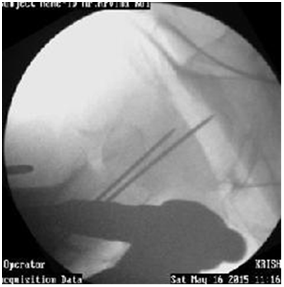

Use of curved femur finder device, retractor push, cannulated curved awl to pass the guide wire in correct direction (Figures 14-17).

Figure 14 Guide wire in canal deviating medially.

Figure 15 Redirection by Retractor push, Femur finder, Cannulated awl.4

Figure 16 Guide wire going medially sometimes can exits out through fracture and damage neurovascular structures.

Figure 17 Redirected Guide wire in canal.